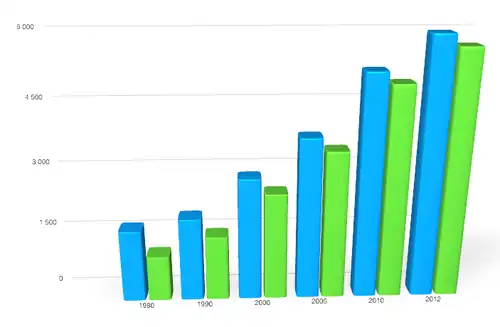

Ces données proviennent des registres nationaux du cancer de France (FRANCIM, qui ne couvrent pas tout le pays)[1]. Attention, sur le graphique les intervalles entre années ne sont pas réguliers

Alors que d'autres cancers comme celui du larynx ont beaucoup diminué en France (et dans d'autres pays), les cancers du pancréas, de 1980 à 2005 ont eu une incidence qui a significativement augmenté (+ 3,8 % chez les femmes, + 2,0 % chez les hommes). L'âge moyen du diagnostic du cancer du pancréas se situe vers 70 ans (INCA, 2012)[5].

Il touche presque deux fois plus souvent l'homme que la femme (sex ratio de 1,8) avec une incidence (en moyenne taux de 7,7 pour l'homme contre 4,7 cas pour 100 000 chez la femme) qui augmente à partir de 50 ans (pic de fréquence à 75 ans pour l'homme, 80 ans pour la femme)[8].

En France, de 1980 à 2010, la mortalité a légèrement augmenté, et proportionnellement plus chez les femmes que chez les hommes (qui restent les plus touchés mais avec un écart diminuant entre hommes et femmes)[1].